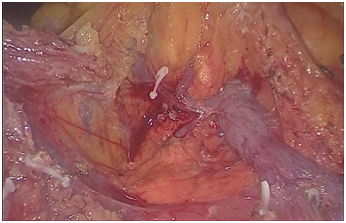

手术图片

腹腔镜直肠癌根治术

腹腔镜胃癌根治术

腹腔镜结肠癌根治术。